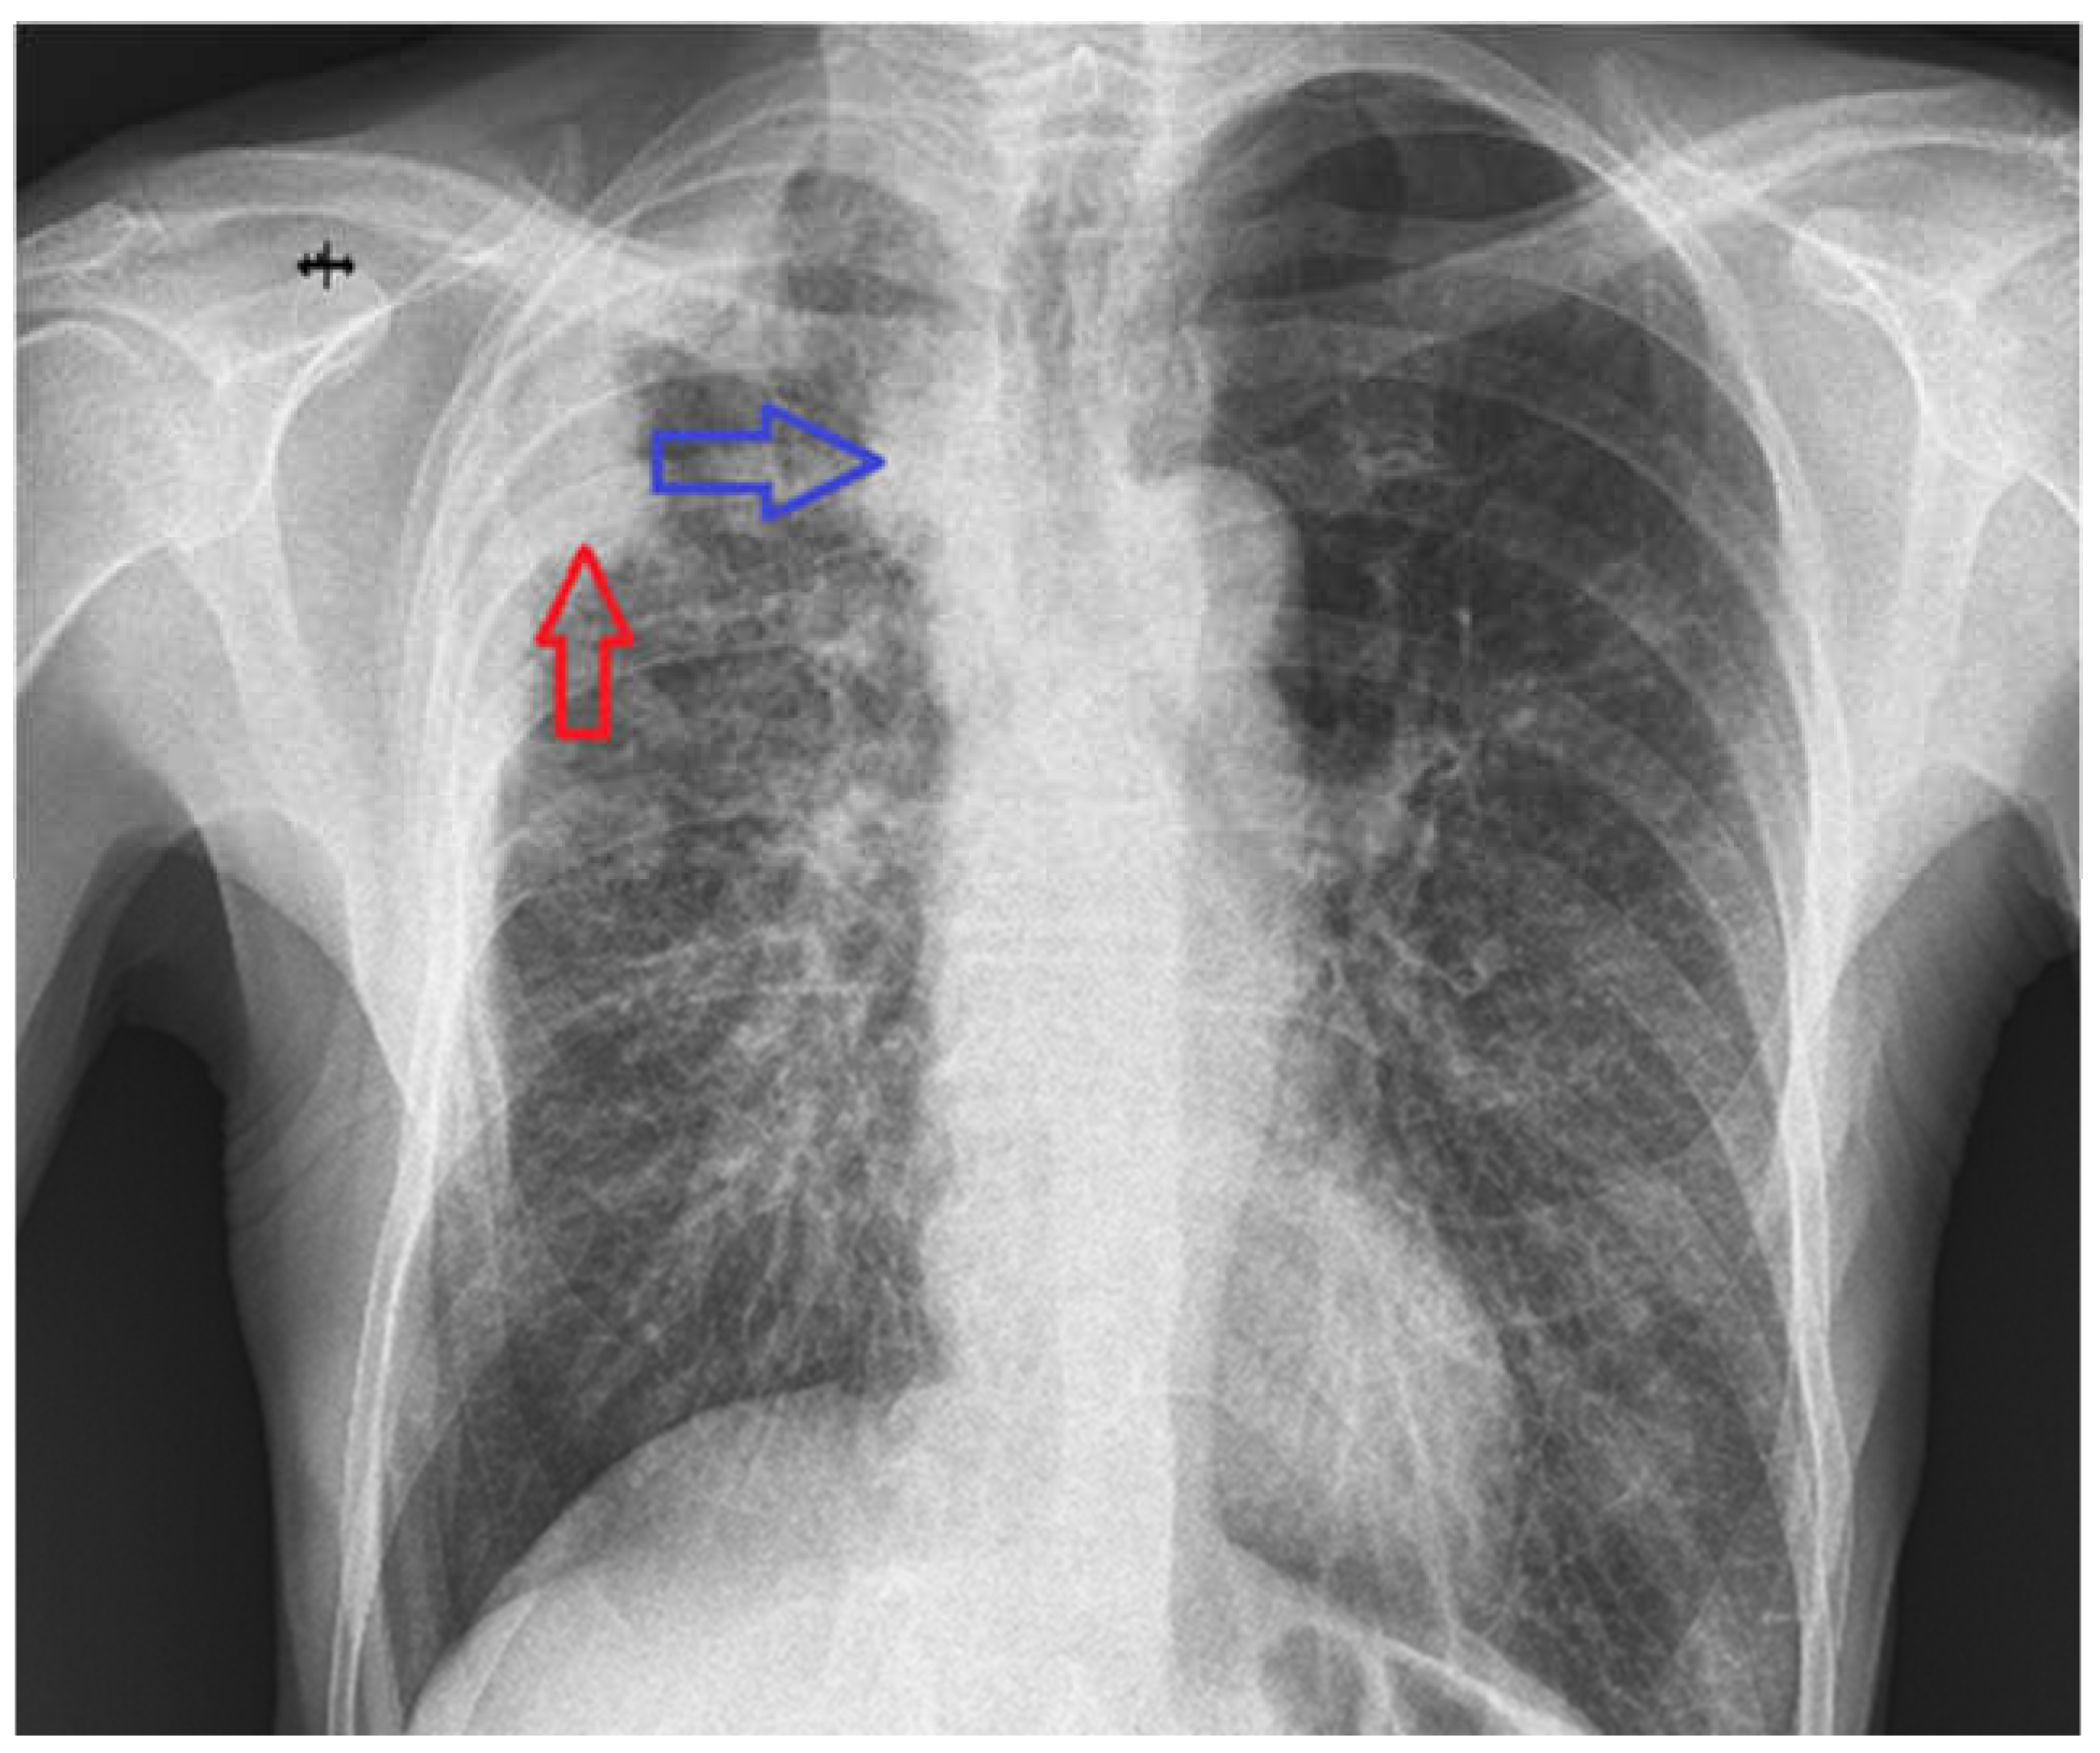

The primary radiologic investigation performed in our clinic was a posteroanterior chest X-ray (Figure 2), which revealed a homogeneous opacity adherent to the right lateral thoracic wall in the upper third (Figure 2—red arrow), a nonspecific widening of the right mediastinum (Figure 2—blue arrow), and also a discreet accentuation of the peribronchovascular markings in the right infrahilar region.

Figure 2. PA chest X-ray—homogeneous opacity, adherent to the right lateral thoracic wall in the upper third and an increased right mediastinal shadow.